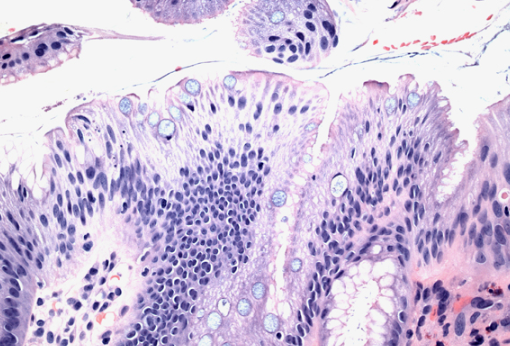

장상피화생은 위 점막이 장 점막처럼 바뀌는 현상입니다. 위 점막은 본래 산성 환경에서 잘 버틸 수 있도록 구성되어 있지만, 오랜 기간 위염이나 헬리코박터균 등에 의해 자극을 받을 경우 장 세포처럼 변형되기도 합니다. 이는 위의 방어기능이 약해졌다는 신호로 볼 수 있지요.

하지만 중요한 건 그 '가능성'이 존재한다는 것입니다. 저도 검색을 통해 알게 되었는데, 특히 장상피화생이 '광범위하거나', '불완전형'일 경우 위험도가 올라간다는 연구 결과들이 있었습니다. 물론 이것이 모든 사람에게 동일하게 적용되는 것은 아니며, 생활습관과 유전, 감염 상태 등 복합적인 요소에 의해 결정됩니다.